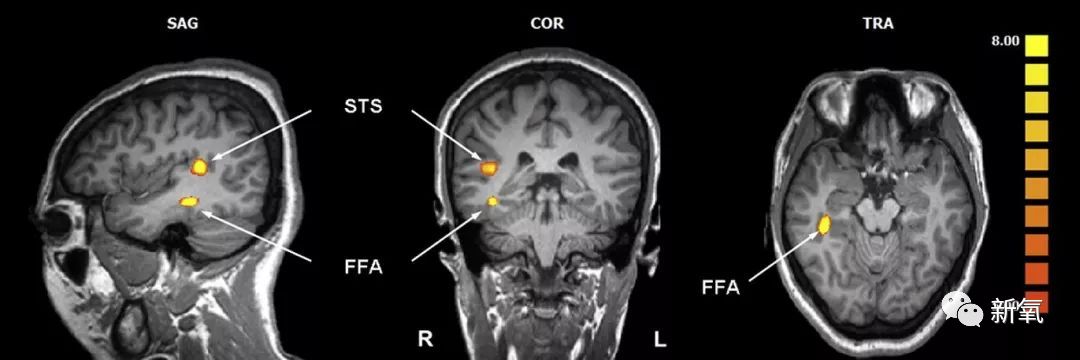

因为我们在看两个长得相似的人时,大脑的FAA脑区会开始活跃进行人脸面部识别。但这个过程是从整体出发,先看面部轮廓、发色、五官排布这种大面积整体的部分,只要这部分相似了就会自动归类于两个人长得像。

然后才会去看小细节,比如眉毛的弧度、瞳孔的颜色之类的。

所以说那些相似的“双胞胎”并不是完美复制,只是因为大部分特征相似,人脑就会自动将其归于一致。拆分开小细节,还是会有很多不一样的地方。